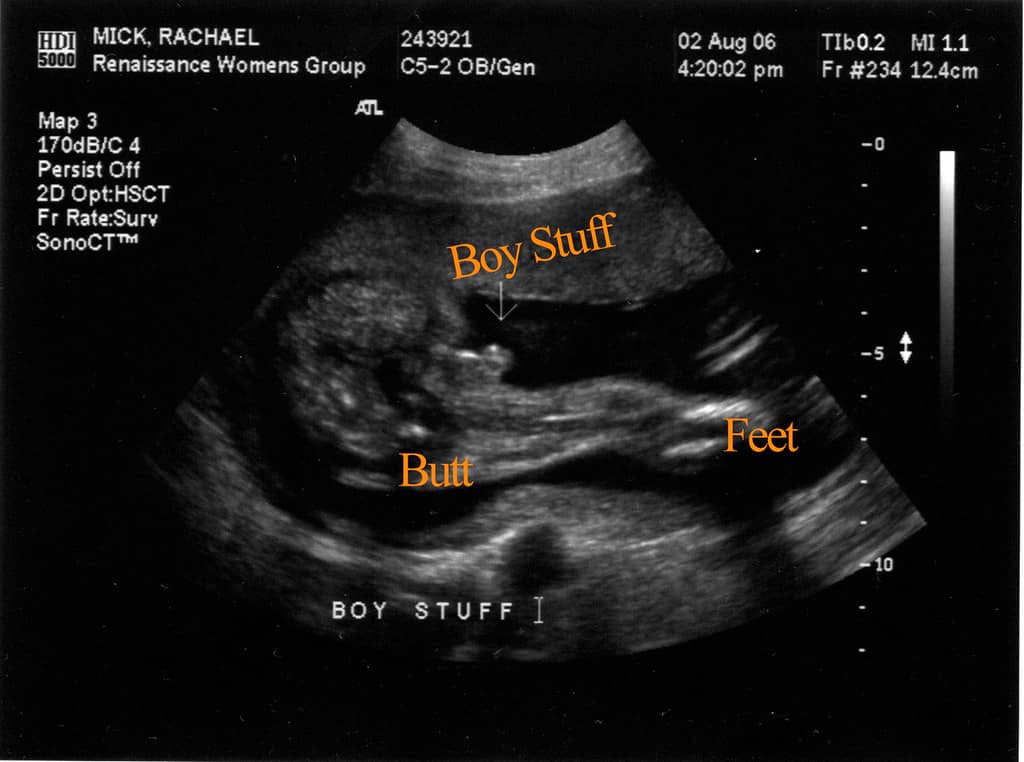

अपनी गर्भावस्था की अल्ट्रासॉउन्ड रिपोर्ट पढ़ने के लिए सबसे पहले हर अल्ट्रासाउंड में EDD (estimated delivery Date ) तथा LMP (लास्ट मेन्स्त्रुअल पीरियड )के बारे में जो भी जानकारी दी जाती है उसका मतलब यह है कि प्रेग्नेंट होने से पहले महिला की लास्ट पीरियड किस डेट में आयी थी और EDD का मतलब होता है डिलीवरी किस तारिख को हो सकती है, दरअसल मे डिलीवरी की तारीख पक्की नहीं होती है। लेकिन फिर भी अंदाजा लगाया जा सकता है कि डिलीवरी इस तारिख के पहले या आगे हो सकती है और लेबर पैन शुरू हो सकता है।